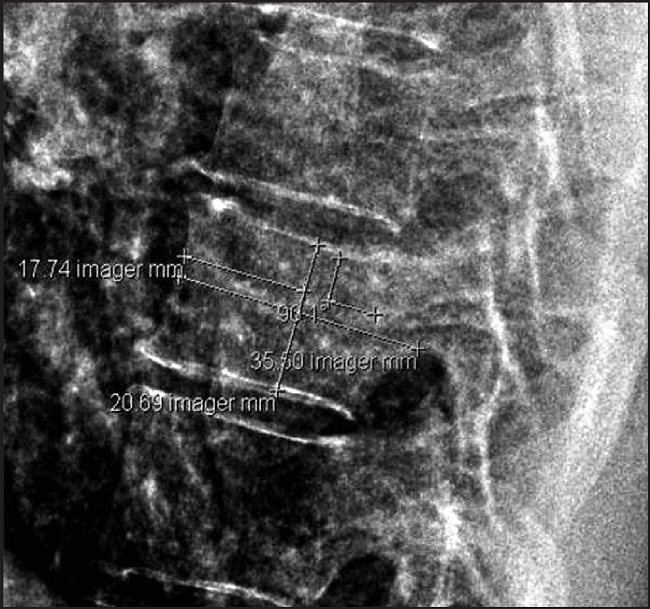

As variables, sex, age, body mass index (BMI), and with a chest lateral plate, not rotated, and in the eighth dorsal vertebra, we calculate his length (LVD8) and his height (HVD8), measured in mm. Figure.

Finally, we applied a comparative study of average of height and vertebral index (VI) results: VI=10 x LVD8/(HVD8 x stature).

Results: 90 patients were analyzed.

20 patients in the study group (222%): 48.1% female, 48.6 years old, 38.2 BMI, and VI 11.6 Meters-1. And 70 patients in the control group (77.8%): 51.1% females 45.15 years old, 26.2 BMI, and VI 11.2 Meters-1. The comparative analysis of avera-ges does not show any significant dif-ferences in the index or in the stature of these patients.

Conclusion: It is a small study, and according to height or the created index, it does not seem that obesity in development modifies the overall height or the vertebral parameters. In addition, the index gives a stable value regarding the sex of both populations in the eighth dorsal vertebra.